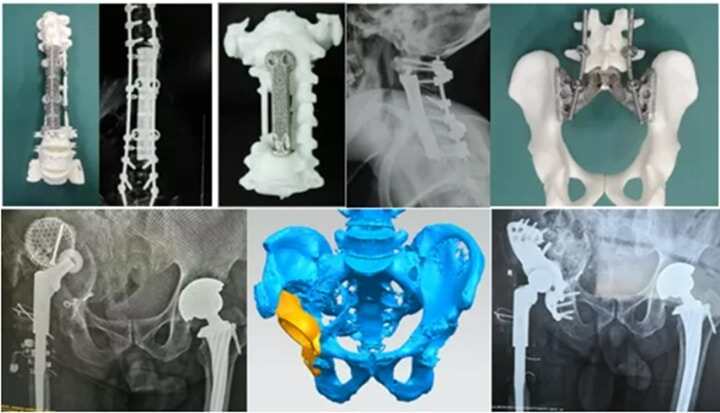

全國(guó)首例3D打印定制鋼板成功植入!從“風(fēng)口”到“風(fēng)向”,骨科企業(yè)爭(zhēng)相入局

近日,全國(guó)首例使用3D打印定制化鋼板”進(jìn)行股骨遠(yuǎn)端粉碎性骨折復(fù)位內(nèi)固定手術(shù)在北京積水潭醫(yī)院成功實(shí)施。